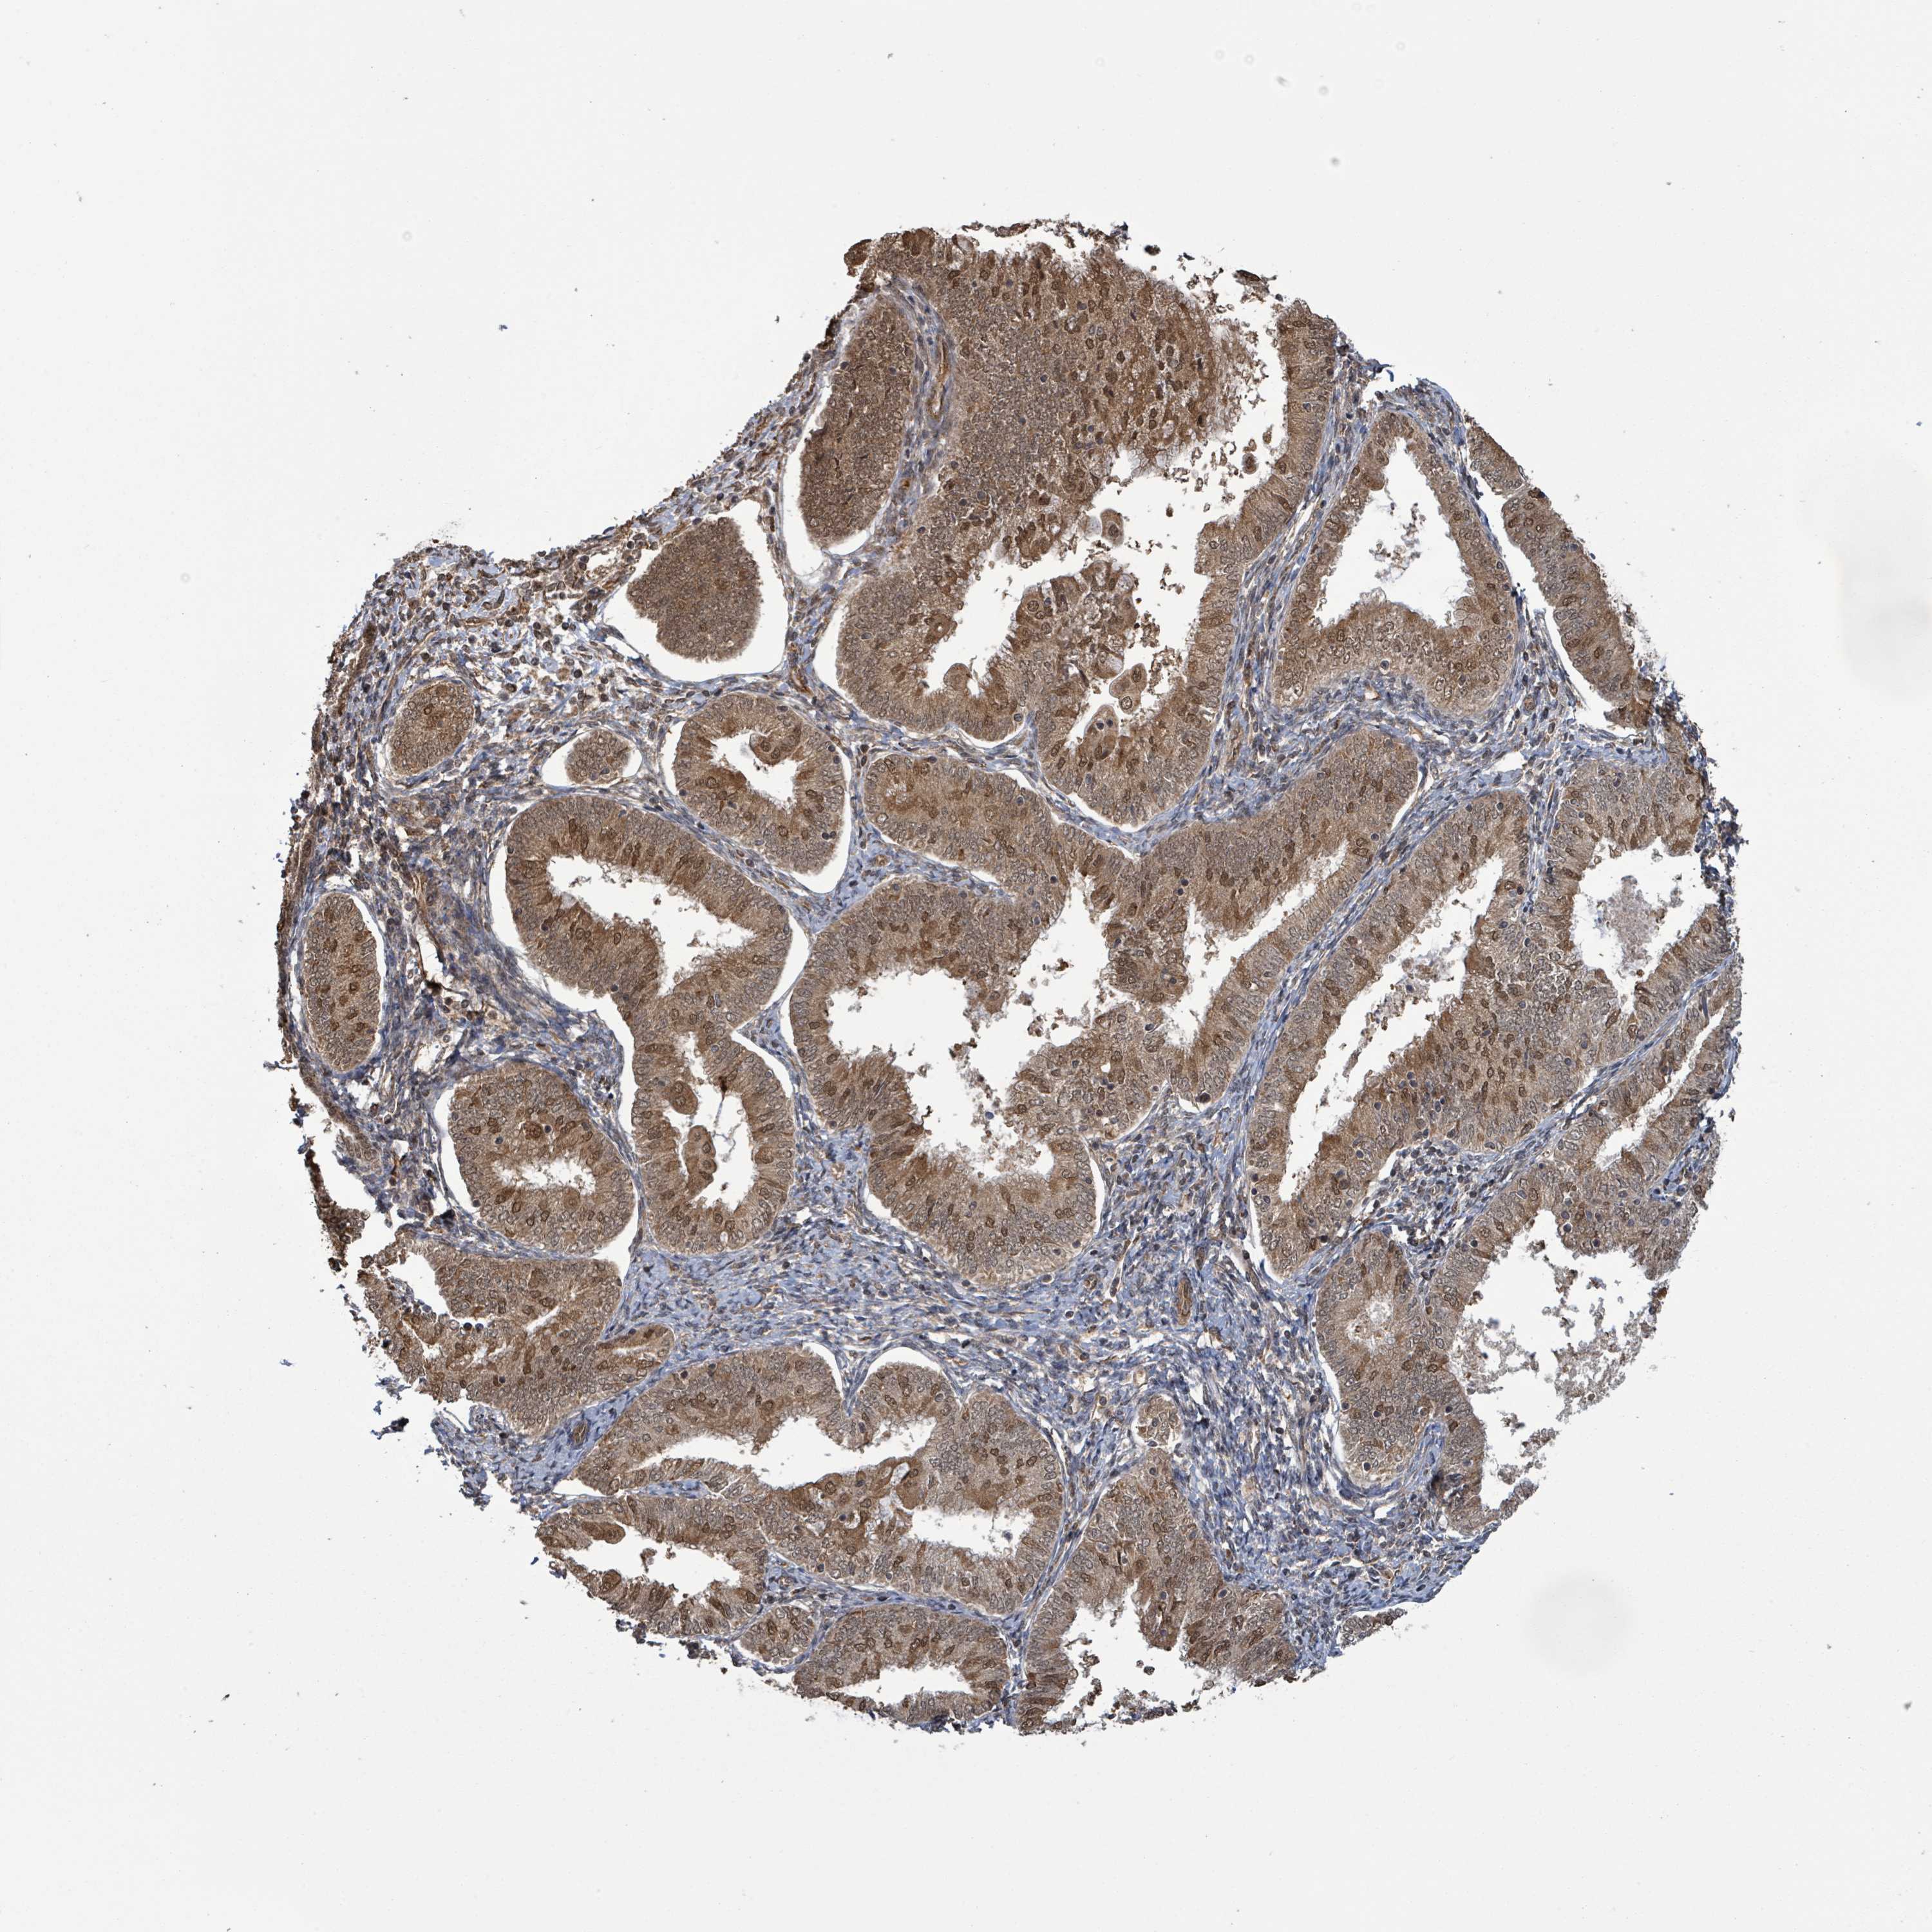

ENDOMETRIAL CANCER - Protein expressioni

A mouse-over function shows sample information and annotation data. Click on an image to view it in a full screen mode. Samples can be filtered based on level of antibody staining by selecting one or several of the following categories: high, medium, low and not detected. The assay and annotation is described here.

Note that samples used for immunohistochemistry by the Human Protein Atlas do not correspond to samples in the TCGA dataset.

Antibody stainingi

Antibody staining in the annotated cell types in the current human tissue is reported as not detected, low, medium, or high, based on conventional immunohistochemistry profiling in selected tissues. This score is based on the combination of the staining intensity and fraction of stained cells.

Each image is clickable and will lead to virtual microscopy that enables deeper exploration of all samples and also displays staining intensity scores, fraction scores and subcellular localization as well as patient and tissue information for each sample.

Antibody HPA044617

Antibody HPA052450

Staining

High

Medium

Low

Not detected

Intensity

Strong

Moderate

Weak

Negative

Quantity

>75%

75%-25%

<25%

None

Location

Nuclear

Cytoplasmic/membranous

Cytoplasmic/membranous,nuclear

Adenocarcinoma, NOS